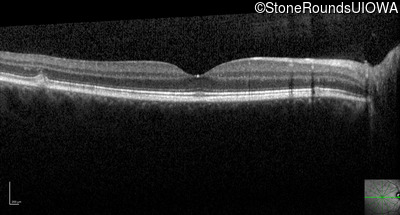

Optical Coherence Tomography - Right - 20/15 -1 sc

Exemplar / OCT Stack